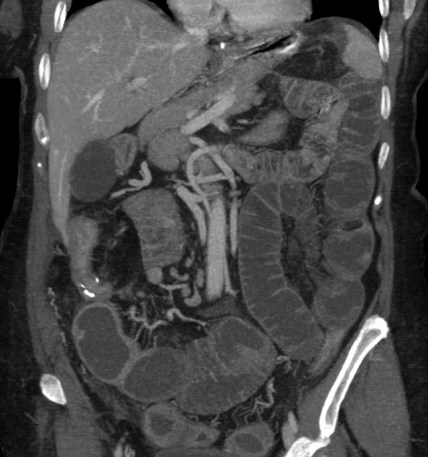

Tomografía Computarizada:

Con sensibilidad y especificidad próximas al 100%, es la técnica inicial de elección ante la sospecha de una obstruccion intestinal. Ante la sospecha firme de obstruccion intestinal, realiza un diagnóstico más preciso, aporta más información adicional y evita retrasos en el diagnóstico.

Hallazgos:

- Distensión proximal a la obstrucción mayor de 3,5 cm en el intestino delgado y mayor de 5 cm en el colon con colapso de asas distales junto con la identificación, siempre que sea posible, de la zona del cambio de calibre (zona de transición), lo que nos permite realizar con mayor seguridad el diagnóstico.

- Si se observan asas dilatadas, independientemente del grado, si no hay colapso de asas distales, el diagnóstico más probable es un íleo paralítico.

- Nivel de la obstrucción: determinado por la zona de cambio de calibre.

- En caso de obstrucción de un asa de colon existirá dilatación del colon proximal. Si la válvula es incompetente existirá también, además, dilatación de intestino delgado.